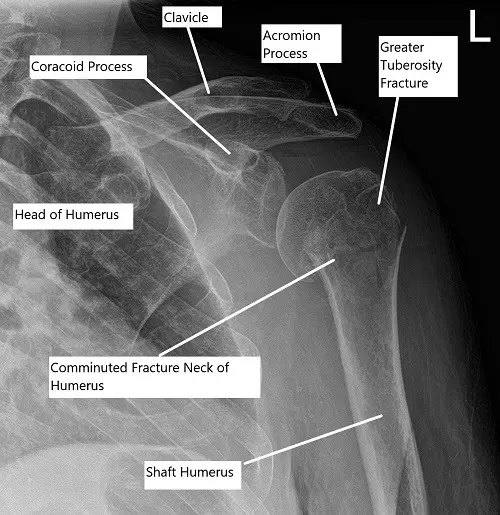

Pre-operative x-ray of the shoulder showing a three-part fracture of the proximal humerus

Radiological studies in the form of an x-ray revealed a comminuted fracture of the humeral head and neck. A CT scan of the left shoulder revealed a comminuted proximal humeral fracture which is impacted and a slightly angulated fracture component at the surgical neck, a slightly displaced fracture fragment at the greater tuberosity, and a subtle nondisplaced fracture at the lesser tuberosity.